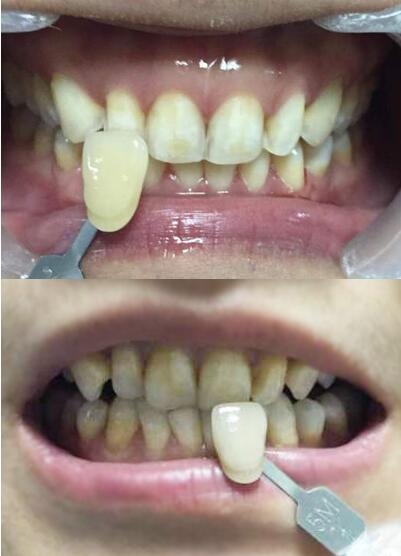

氟斑牙|瓷贴面修复——比基色牙